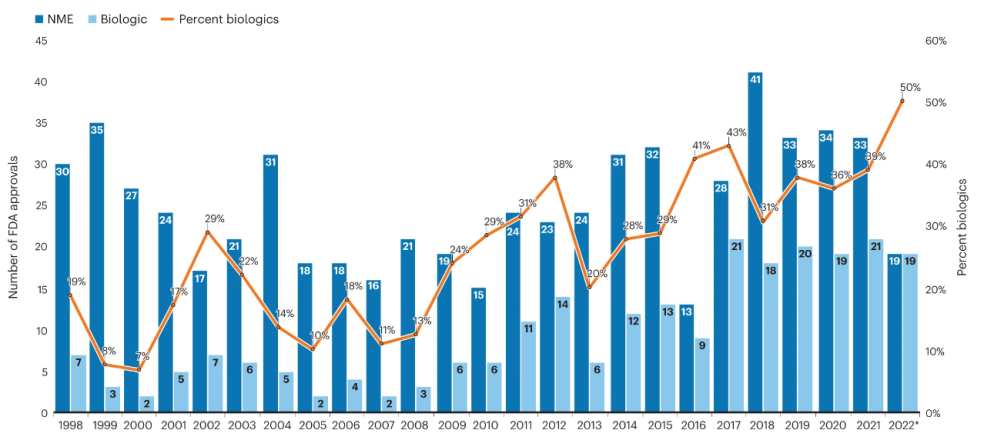

9.新药批准减少,生物制剂占比增加

2022年新药批准数量较2021年下降25%,降至2016年以来的最低水平。但创新并没有放缓:抗体-药物偶联物(ADC)、双特异性蛋白以及细胞和基因疗法等新模式约占2022年批准的三分之一,帮助推动生物制剂的批准首次领先于小分子。

FDA的药物批准,图片来源:Brain light/Alamy Stock Photo